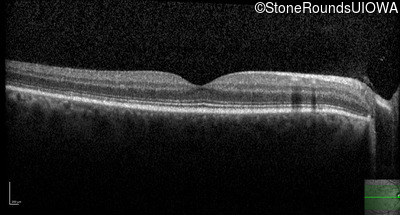

AR Stargardt Disease (IIA)

Age at visit: 30 years

This 30 year old asymptomatic man had fundus abnormalities identified incidentally on a routine exam.

Diagnosis & molecular findings

Disease Gene Allele 1 variant(s) Allele 2 variant(s) Inheritance mode

AR Stargardt Disease ABCA4 IVS30+1321 A>G Asn965Ser AAT>AGT AR